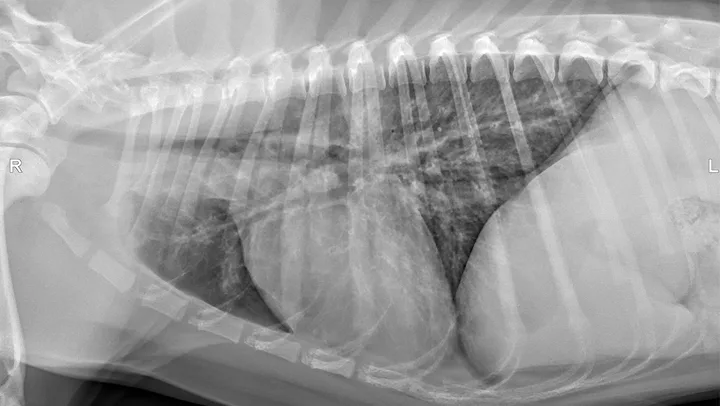

Dogs with bacterial pneumonia are typically presented with acute-onset coughing, lethargy, inappetence, and/or respiratory distress. An inflammatory leukogram and pyrexia, although common, are not always present. Radiographs may reveal an interstitial-to-alveolar pattern with a cranioventral distribution (Figure 1). Atypical distributions can also occur.5

FIGURE 1

(A) Bronchopneumonia. Cranioventral distribution of alveolar disease with air bronchograms. (B) A patchy distribution can be observed on the lateral projection. The changes overlying the heart may be missed in subtle cases.